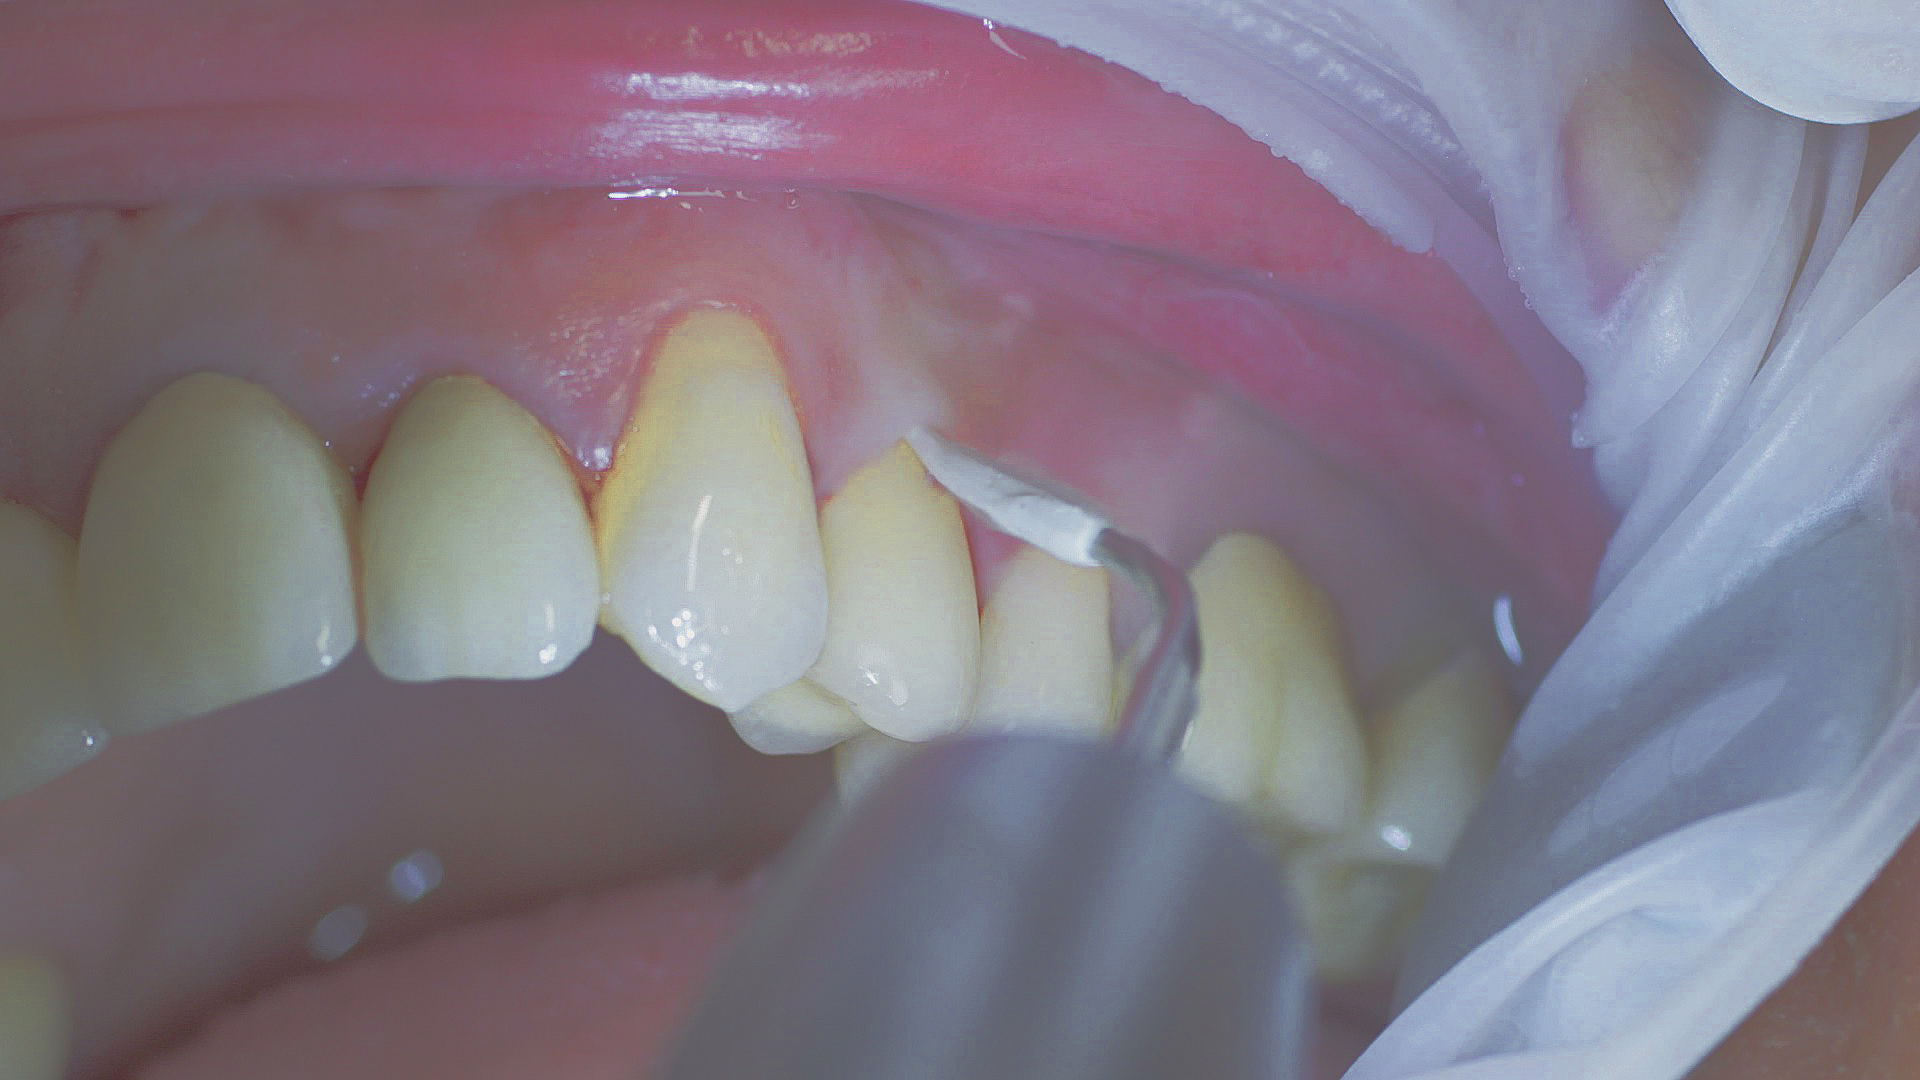

Where necessary, initial periodontal treatment is carried out. First, professional tooth cleaning establishes healthy gingival conditions. In this procedure, calculus (Fig. 1) and biofilm (Fig. 2) are removed as far as the gingival sulcus. In combination with careful instruction on oral hygiene, this gives the patient the basis for long-term freedom from inflammation.15

Calculus removal using an ultrasound

Fig. 1: Calculus removal using an ultrasound (W&H Tigon+ with a 3U tip) is a key part of professional tooth cleaning.